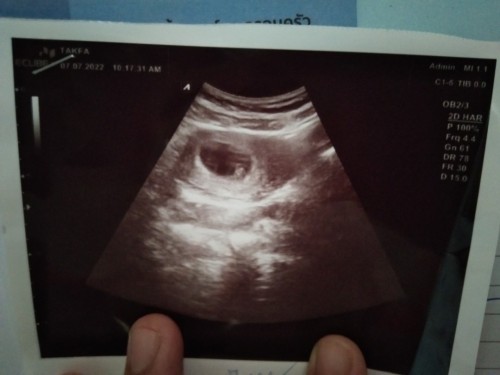

ในถุงครรภ์ใช่ตัวอ่อนน้องไหมค่ะ

กี่วีคคะ อาจจะเป็นไข่แดง

เป็น หัวใจดวงน้อยๆจ้าแม่

ขอบคุณค่ะ ได้เห็นหัวใจดวงน้อยๆเเล้วชื่นใจ